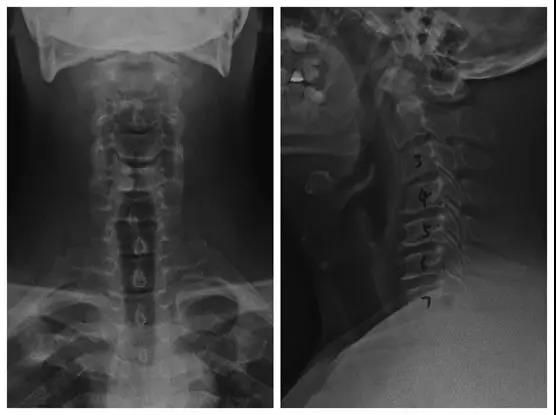

颈椎后路椎板切除减压,C3-6侧块螺钉、C2椎弓根螺钉固定,植骨融合手术

术前X线正侧位片